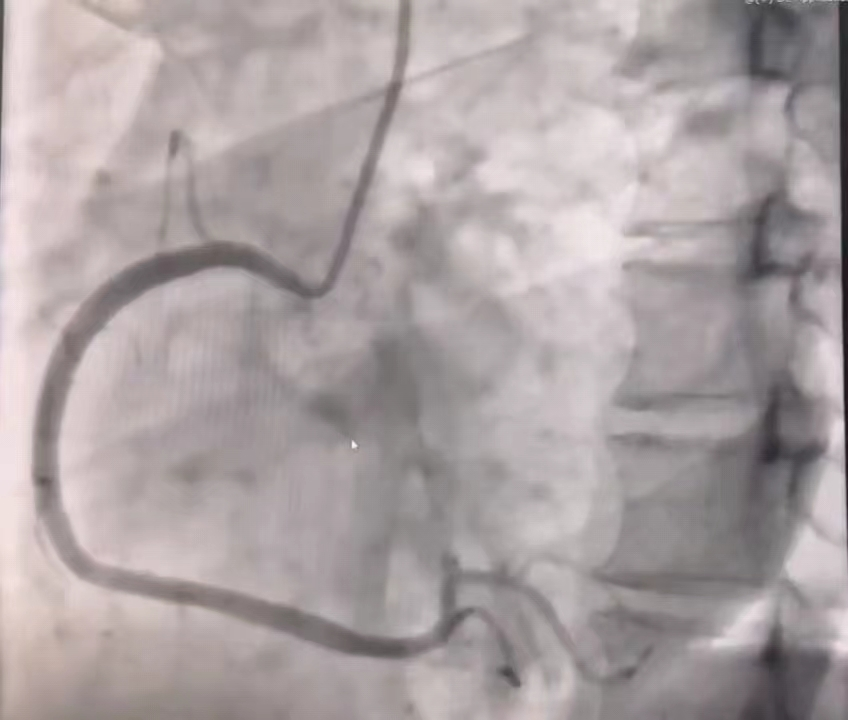

冠脉造影:左右冠脉走行区内未见明显钙化影,左右冠脉开口未见异常,冠脉供血呈右优势型,左主干未见明显狭窄;前降支中段节段性狭窄,最重处30%,回旋支未见明显狭窄,右冠脉未见明显狭窄。见图5。

图5 分别为前降支、回旋支、右冠脉造影结果